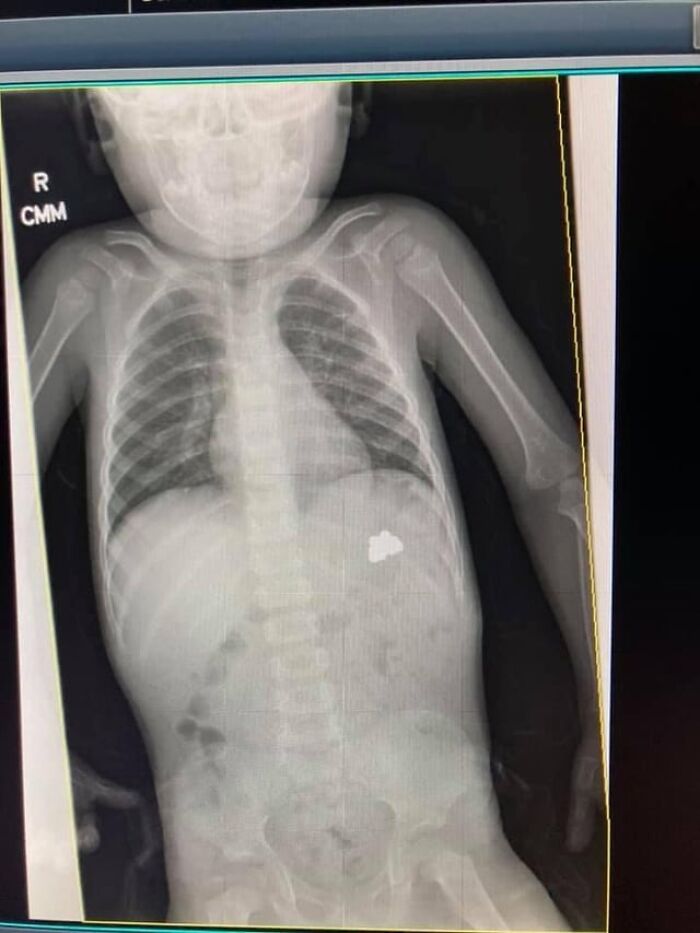

#39 My Son Has Russell Silver Syndrome

When Your Child Has A Very Rare Condition Hospitals Like To Run Tests And Perform Studies To Better Improve Their Knowledge On Rare Conditions. Each Study Makes It Closer To Fully Understanding Rss. Today They Will Perform An Endoscopy Procedure.

Image source: medical